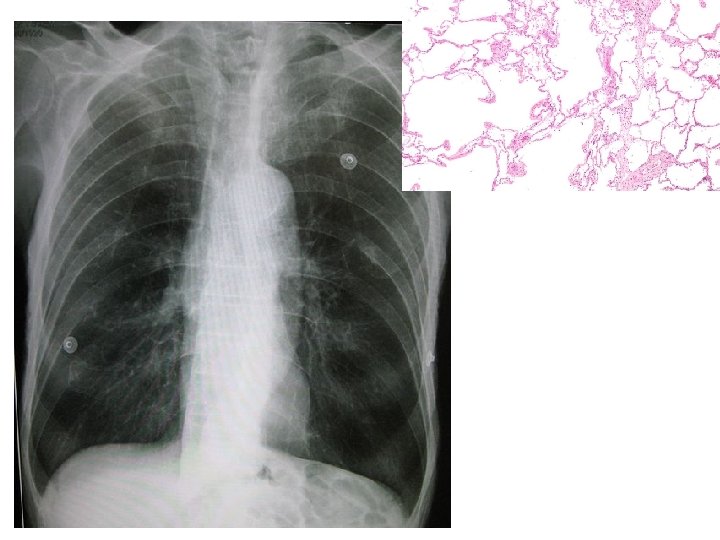

Dohányos COPD-s tüdő

COPD A légutak krónikus, nem visszafordítható gyulladása, amelyet mindennapos köhögés és/vagy nehézlégzés jellemez

COPD Krónikus obstruktív tüdőbetegség • Kb. 500. 000 COPD-s él ma Magyarországon • Közülük kb. 200. 000 -et ismerünk • A COPD a 3 -4. halálok • Az esetek 80 -90%-a a dohányosok közül kerül ki • Nem gyógyítható, de eredményesen kezelhető betegség